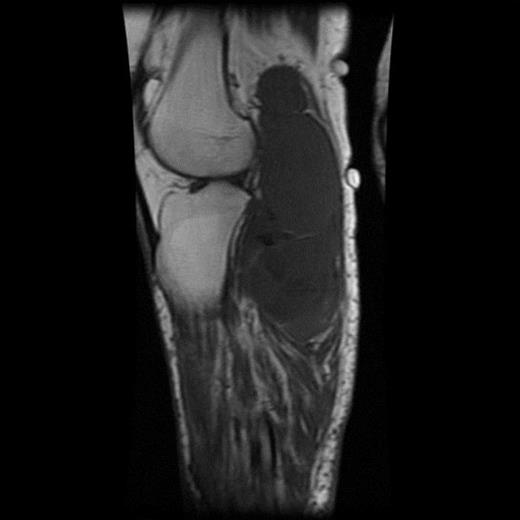

The MRI scan of the right knee (Figs 2 and 3) with gadolinium-enhancement showed a large mass lesion in the posterior aspect of the right knee extending into the popliteal fossa and into the upper third of the right leg having appearance of bursal pathology. Post gadolinium images showed evidence of circumferential rim enhancement but no internal enhancement indicating the presence of a fluid filled lesion. The mass (Figs 4 and 5) measured ∼8.39 × 6.14 × 12.72 cm and was seen between semimembranosus and biceps femoris muscles. There was no evidence of any infiltration of either the sciatic nerve or the popliteal vessels. A likely diagnosis of complicated synovial cyst with a differential diagnosis of haematoma was reported and a provisional diagnosis of Baker's cyst was established.

Post gadolinium-enhanced MRI image showing circumferential lesion.